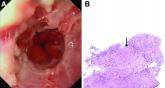

ArticleMarch 2021 - What's your diagnosis?Author:Thomas P. Chapman, DPhilPublish date: February 26, 2021A 49-year-old man presented with symptoms of retrosternal discomfort and mild dysphagia to solids.Read More